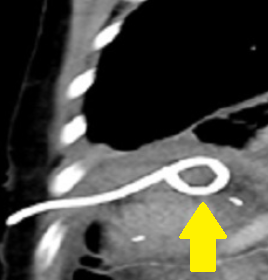

Patient CT, 6th postoperative day. Contrast in the gallbladder fossa. Red arrow — Injured Luschka duct (Courtesy Dr. V. Penopoulos)